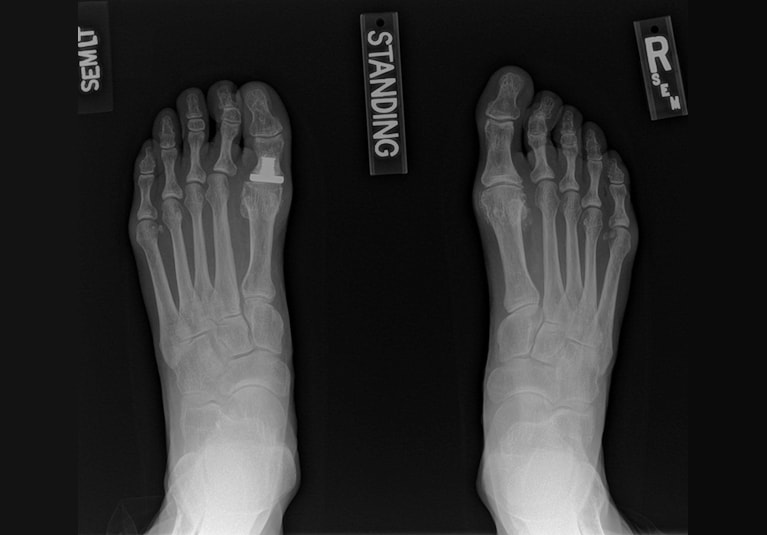

X-rays illustrate the case of a patient who presented at Mayo Clinic in Jacksonville, Florida, with severe stiffness and pain after a first metatarsophalangeal joint replacement. On the left, a preoperative X-ray shows a 1.4-centimeter shortening of the great toe of the left foot, where joint replacement had been performed. On the right, an X-ray three months after revision surgery at Mayo Clinic shows the healed bone graft and restored toe length. The patient is now pain-free.

Mayo Clinic's salvage surgery uses an interpositional graft that has been contoured from a patella wedge. "The density of that bone allows us to fill the bone defect after we remove the implant from the big toe. We can generally lengthen the toe by 10 to 12 millimeters, which is enough to relieve the transfer metatarsalgia," Dr. Whalen says.

The precise amount of toe lengthening depends on factors such as soft tissue scarring and the patient's circulatory health. The structural bone graft fully incorporates by about eight to 16 weeks after surgery. Successful healing occurs in approximately 90% of patients who comply with postoperative restrictions.